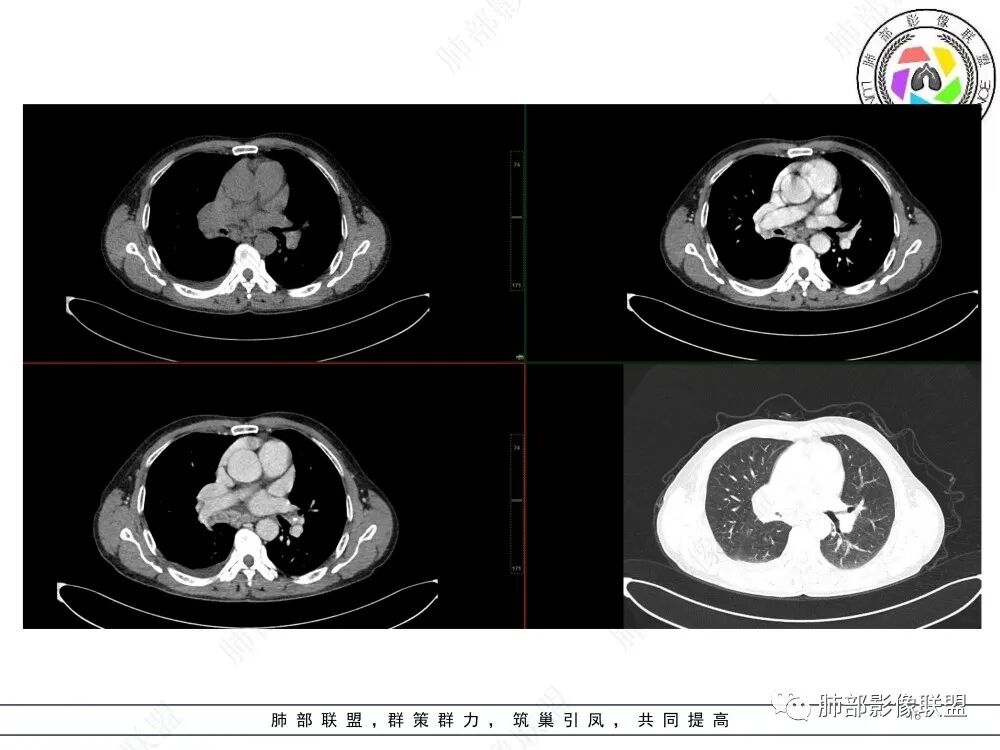

杨宏刚: 老年男性,咳嗽咳痰,CRP升高。右肺支气管血管束呈指套状改变,支气管呈鼠尾状狭窄,相应肺叶大片实变,增强见血管造影征,走行尚可,纵隔多发淋巴结肿大。小细胞冰冻纵隔不明显,考虑恶性,鳞癌,并阻塞性肺炎肺不张。鉴别结核。

屈运良: 老年男性,慢刺激性咳嗽,纵隔内见肿大淋巴结,右肺门肿块及肿大淋巴结融合呈块状,下叶支气管狭窄呈针孔样,肿块沿支气管血管束走行,明显强化,肿块内见走行正常的血管影,纵隔及右肺门淋巴结有融合及环状强化,老年高危病人,首选恶性,尽管淋巴结有环状强化,但肿块整体强化不支持TB,综合考虑支持小细胞癌。

宋明亮:老年男性患者,咳嗽咳痰胸疼。右肺下叶实变,肺门肿块,纵隔淋巴结增大。考虑中心型肺癌,鳞癌可能。

这应当是一相当典型病例。

1.支气管腔内强化结节影,管腔阻塞,阻塞性肺炎(肺炎、肺不张),符合引流途径的肺门纵隔淋巴结肿大。符合恶性新生物判断,腔内结节影均匀强化,一般也不符合异物或结核等肉芽肿性炎。

2.支气管密切相关新生物有肺鳞癌、小细胞癌、类癌、涎腺类肿瘤等……

最常见的显然是鳞癌,这点相当重要,管腔内结节,阻塞彻底,阻塞性肺炎,又是老年男性患者等等。

3.小细胞癌转移更早,淋巴结肿大更夸张,易出现纵隔冻结等。